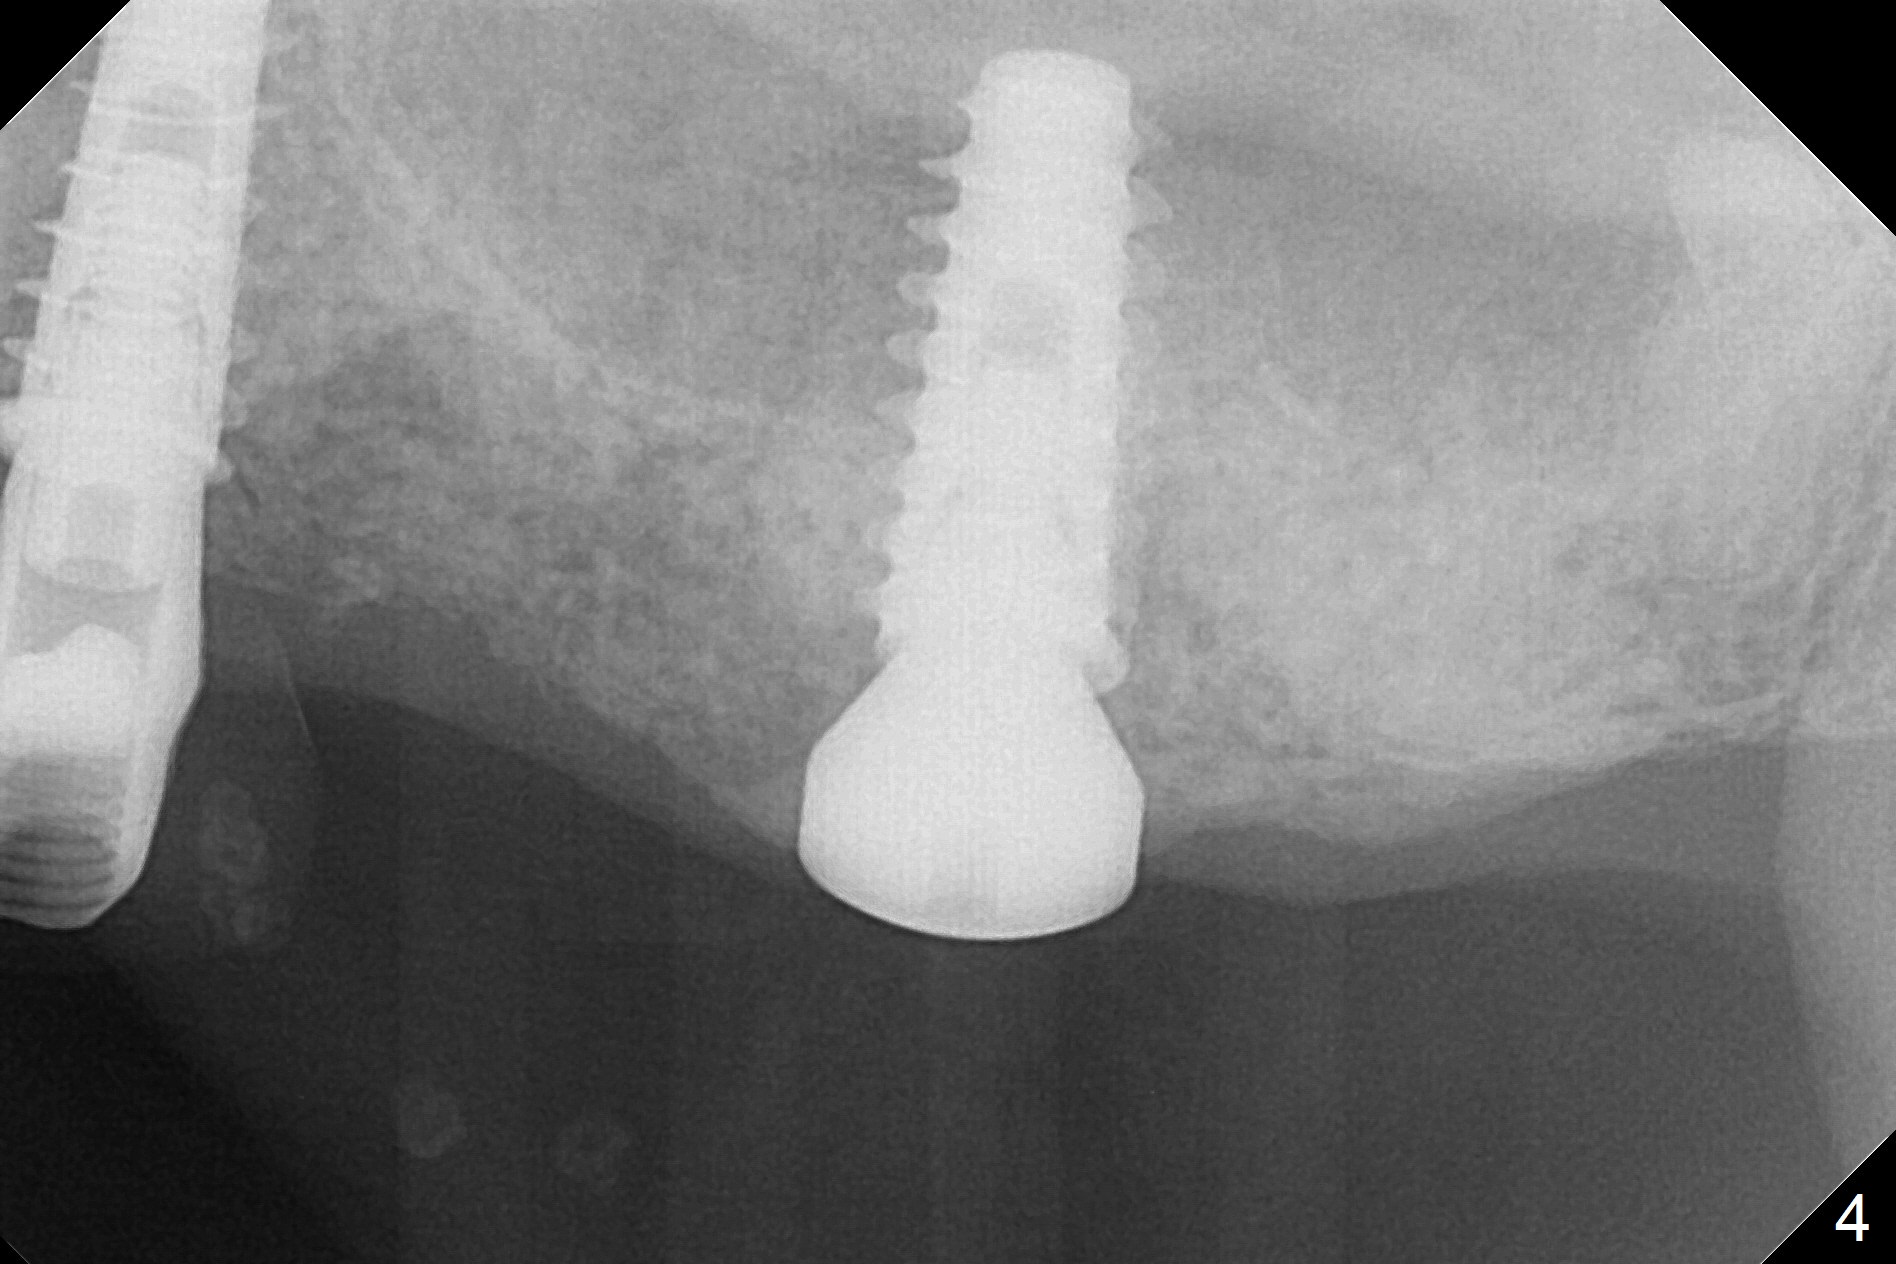

A fistula is found apical to #13 immediate implant 9 months postop (Fig.1).  It is curetted without bony defect.  Osteotomy at #15 is accomplished with traditional tapered osteotomes from 2 to 5 mm for 11 mm deep.  Although the patient is a little uncomfortable with tapping (as compared to Magic Expanders), a 4.5x11 mm dummy implant is placed 2 mm subgingival with primary stability (Fig.2).  Finally a 5x11 mm IBS implant (2 mm longer than the previous one) is placed with insertion torque > 50 Ncm; a 6x2 mm healing abutment is placed (Fig.3,4).  The advantages of the flapless surgery (because of the wide ridge) include no allograft or suture.  The fistula apical to #13 implant disappears 3 days postop (Fig.5), while the gingiva attaches to the healing abutment at #15 (Fig.6).